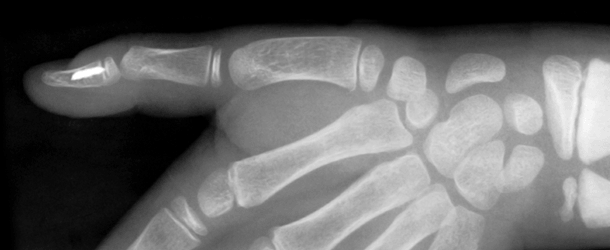

Osteopenia is said to be the precursor of Osteoporosis. Osteopenia is the beginning of bone disease and means weak bone. Osteoporosis is the thinning of bone tissue and loss of bone density over time. Researchers estimate that about 1 out of 5 American women over the age of 50 have osteoporosis. About half of all women over the age of 50 will have a fracture of the hip, wrist, or vertebra (bones of the spine). Osteoporosis occurs when the body fails to form enough new bone, when too much old bone is reabsorbed by the body, or both. Bones are actually living tissues with many layers consisting of collagen, protein and minerals and these layers are tightly packed. In fact, our bones are so strong, that some bones can withstand hundreds of pounds of pressure without snapping. That being said, there is always room for a freak accident where a break happens and it just doesn’t seem right. If you do not get enough calcium, or if your body does not absorb enough calcium from the diet, bone production and bone tissues may suffer. So what are the causes of Osteopenia and Osteoporosis?